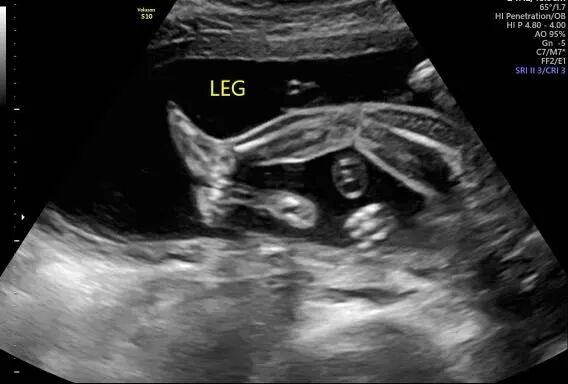

宝宝接近四个月的时候,爱妈Y再次进行了B超检查,此次检查清晰显示出一个健康可爱的女宝宝。爱妈随即将B超照片发送给准妈妈,并满心欢喜地赞叹宝宝的可爱。看到宝宝健康成长,准妈妈既感动又高兴,对爱妈的细心照料表示深深的感激。 准父母成功匹配后,我们会为双方建立一个交流群,这样准父母和爱妈可以方便地进行沟通。在这个群里,爱妈和我们的客服团队会定期更新检查结果和宝宝的成长情况。我们都非常期待下次见到宝宝的时刻!